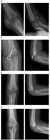

1. 当院初診日の転位量が2.0mm以上であった6例は手術を行ったが、初診日までの外固定肢位は全例肘屈曲83°以下

1. 初診日の転位量が2.0mm未満であった17例は、前腕回内、肘屈曲96~120°で外固定し、全例骨癒合。可動域も良好。

転位量2mm未満の小児上腕骨外側顆骨折は、不適切な外固定が行われて転位することも多いが、前腕回内肘関節鋭角屈曲位での適切な外固定を行えば問題なく治癒することがほとんどである。